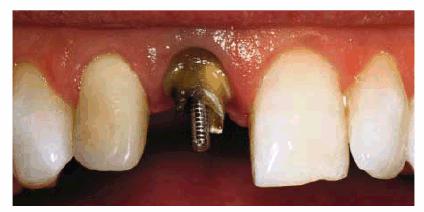

posts were constructed and cemented on the two maxillary incisors (Figur 323s1823d es 18-7E to

H). Final

preparations were made, and impressions for aluminous porcelain crowns were

made. The two crowns were seated (Figur 323s1823d es 18-7I

and J Figur 323s1823d e 18-7K is a radiograph of the teeth at the

end of treatment.

Figur 323s1823d e 18-7E to H: Next, two posts and cores were constructed for the endodontically treated teeth.

Figur 323s1823d e 18-7I and J: Two aluminous porcelain crowns were constructed and inserted on the central incisors.